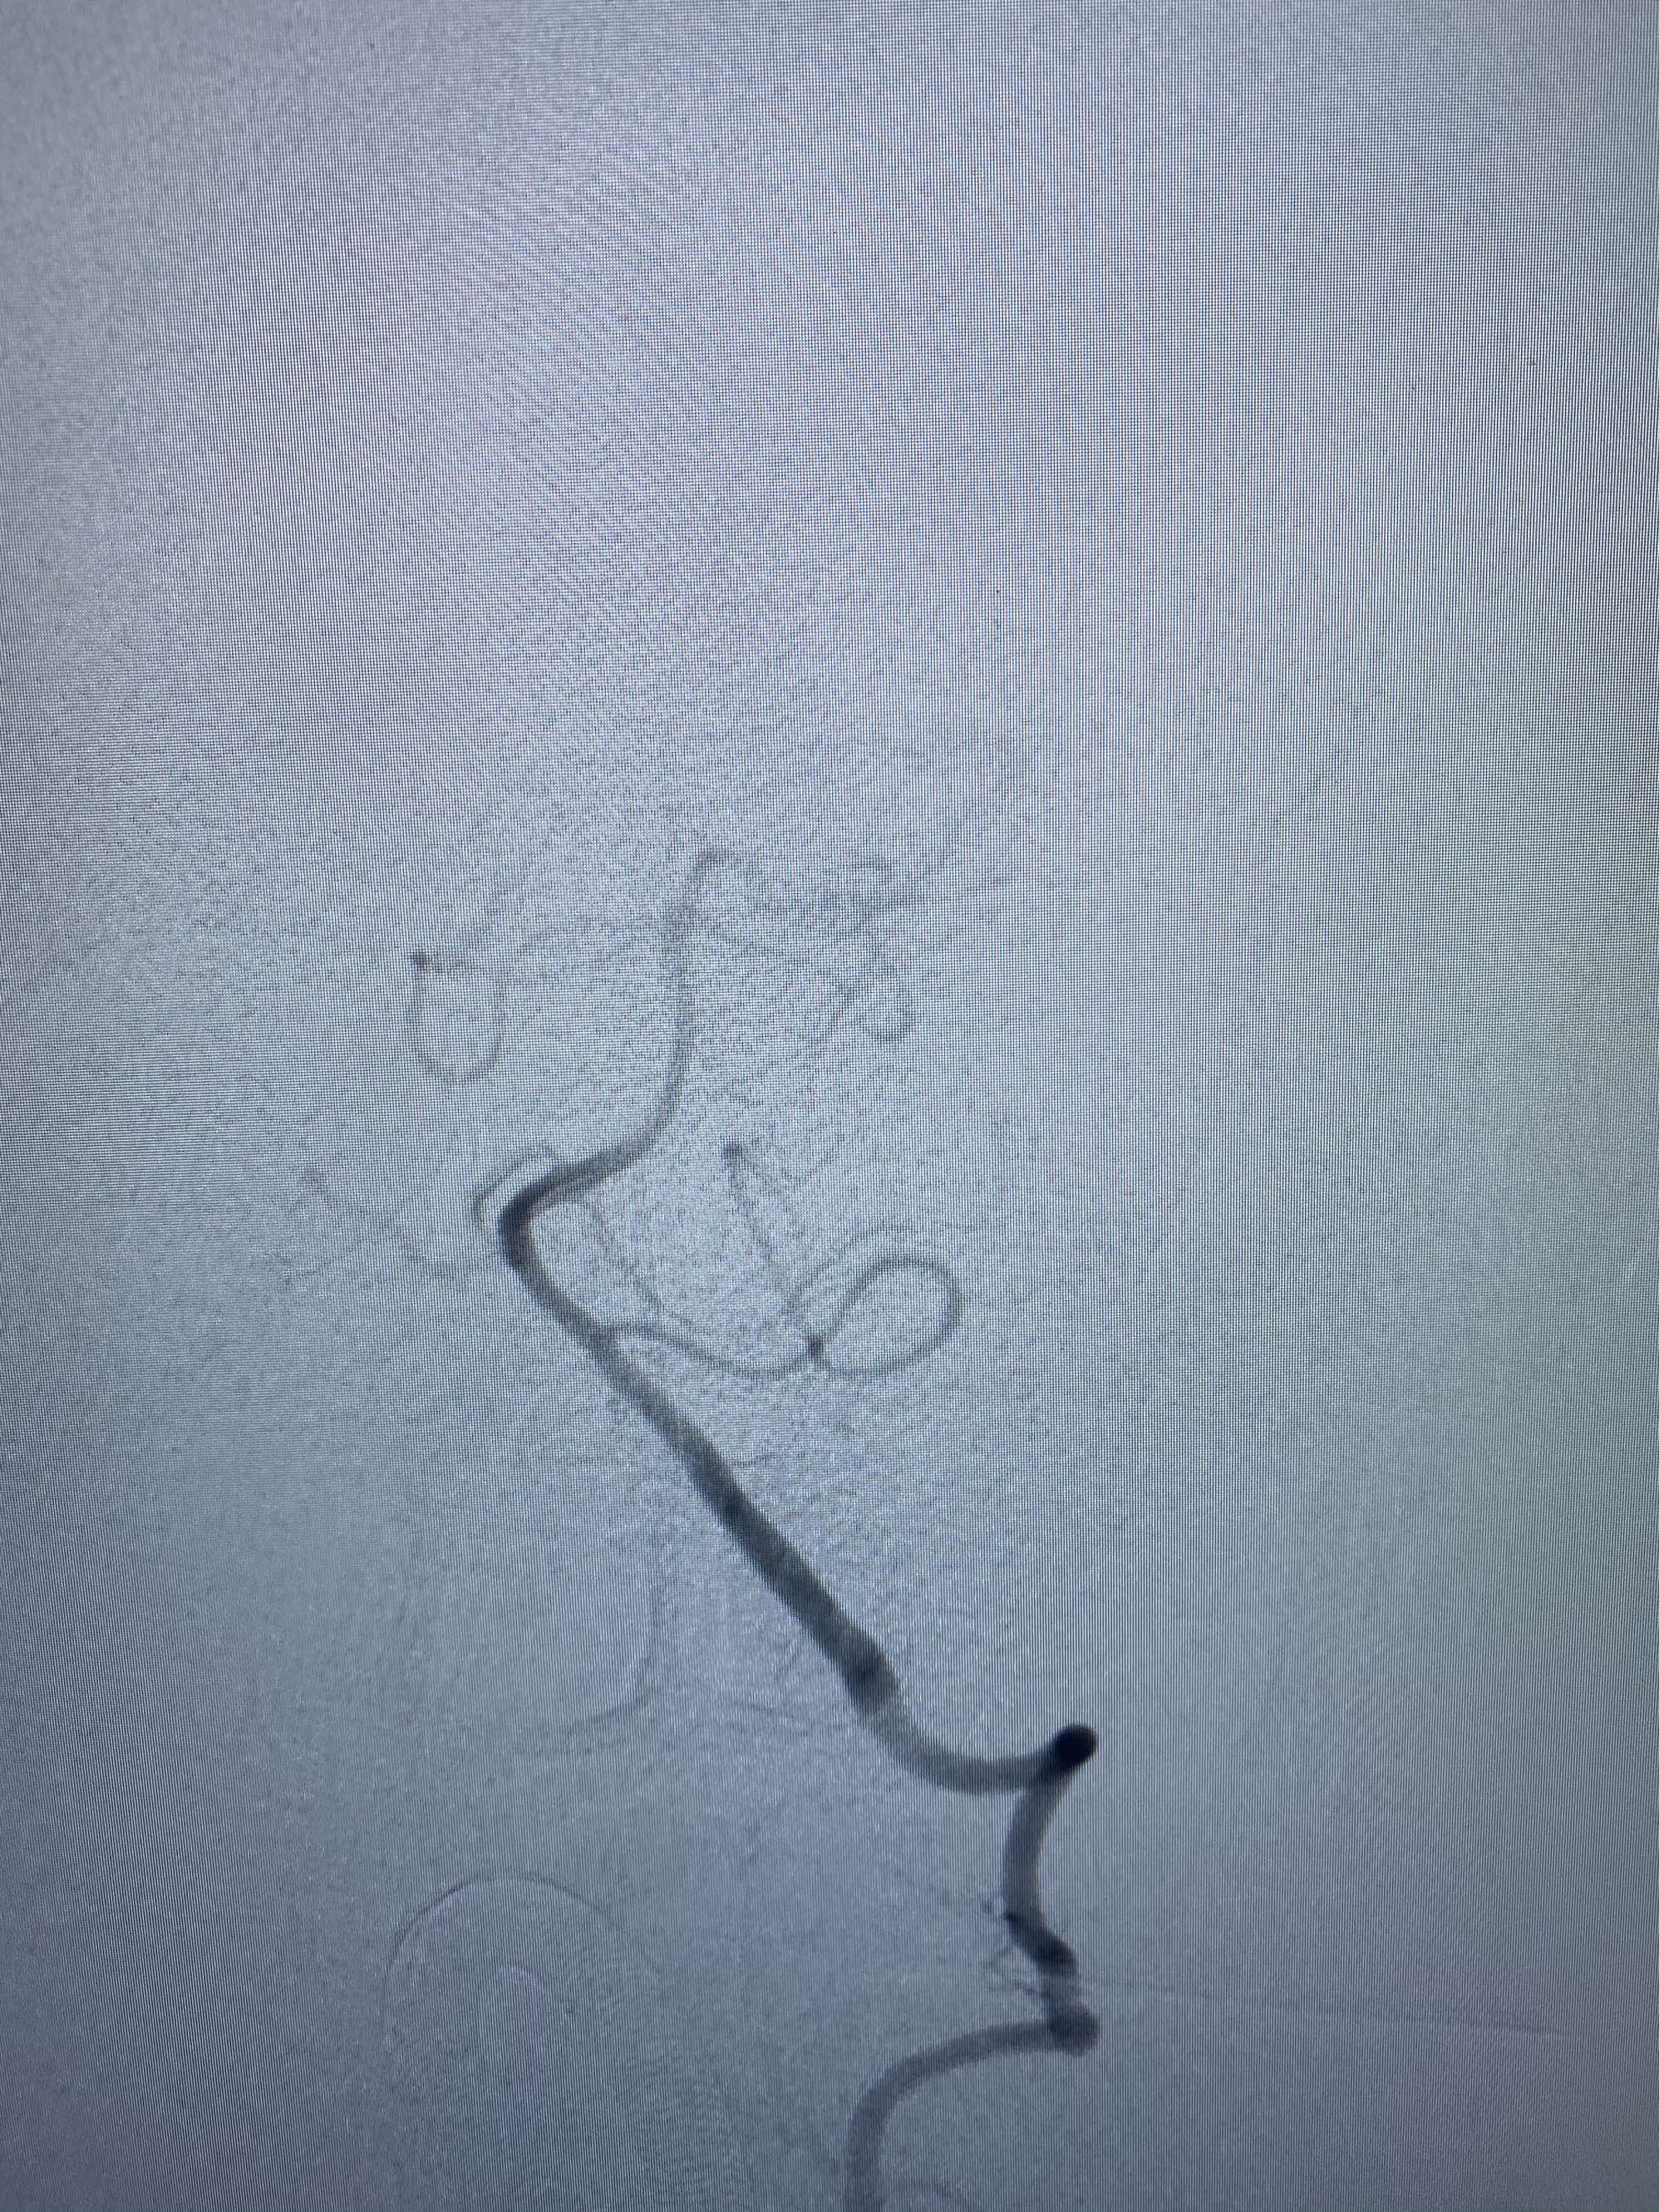

MLS,M79Y,sah,双侧MCA烟雾病,Heubner返动脉瘤,前交通段开窗,细支发出Heubner返动脉,瘤颈细长,瘤颈口比微导管细,弹簧圈2mmx3cm“隔山打牛”填塞治愈,Heubner返动脉保留。

该患者术后2天观察神志清楚,四肢活动正常。